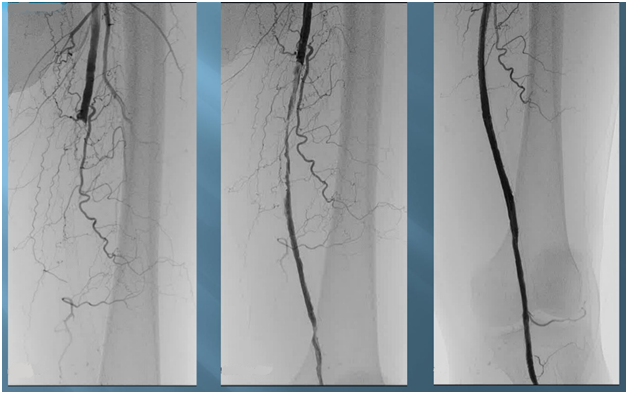

Хроническая окклюзия артерий: причины, симптомы и лечение